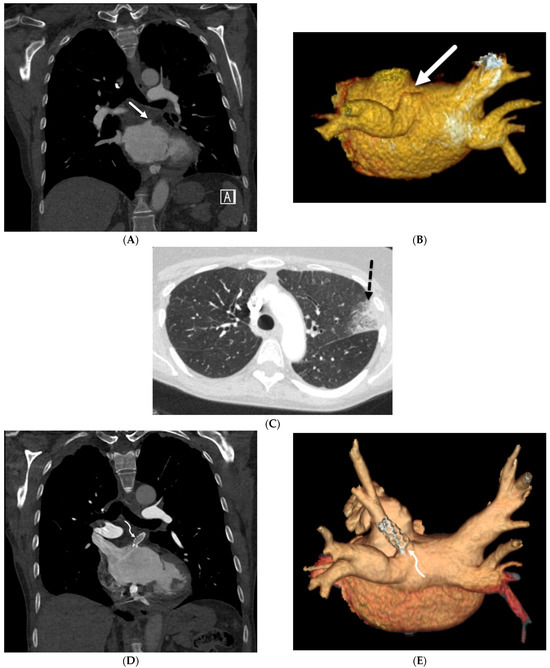

4.7. Pulmonary Vein Stenosis (PVS)